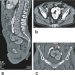

Abbildung 5a-c: Kuchenniere CT-Angiographie. (a): Sagittale Schnittebene mit Darstellung der ventralen Ausrichtung des Hilus; (b): axiale Schnittebene mit Visualisierung beider Äste der Nierenarterie (weißer Pfeil); (c): koronare Schnittebene mit Darstellung einer Nierenarterie (roter Pfeil) und der lobulierten Oberfläche der Kuchenniere. |

CT-Angiographie. (a): Sagittale Schnittebene mit Darstellung der ventralen Ausrichtung des Hilus; (b): axiale Schnittebene mit Visualisierung beider Äste der Nierenarterie (weißer Pfeil); (c): koronare Schnittebene mit Darstellung einer Nierenarterie (roter Pfeil) und der lobulierten Oberfläche der Kuchenniere. |